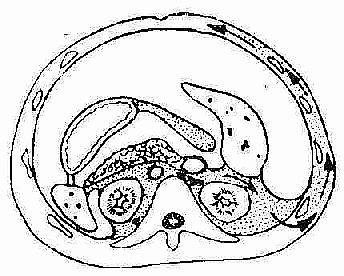

4.皮肤瘀斑部分病人脐周皮肤出现兰紫色瘀斑(Cullen征)或两侧腰出现棕黄色瘀斑(Grey Turner征),此类瘀斑在日光下方能见到,故易被忽视。其发生乃胰酶穿过腹膜、肌层进入皮下引起脂肪坏死所致,是一晚期表现(图2-76)

出血经腹膜后间隙到达皮下脂肪,引起一侧或双侧胁腹部瘀斑和变色(Grey Turner征)"/>

出血经腹膜后间隙到达皮下脂肪,引起一侧或双侧胁腹部瘀斑和变色(Grey Turner征)"/>

图2-76 出血经腹膜后间隙到达皮下脂肪,引起一侧或双侧胁腹部瘀斑和变色(Grey Turner征)。铁盐沉着可引起永久性变色。